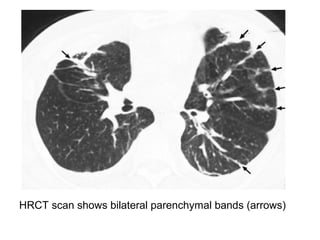

HRCT scan shows bilateral parenchymal bands (arrows)